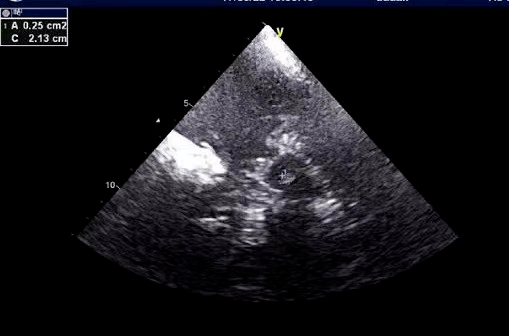

黑质超声

经颅超声在帕金森病痴呆症状中的声像图表现

经颅脑实质超声检查(tcs).

检查手段方面包括:头多巴胺转运蛋白dat-pet或ect检测,中脑黑质超声

【黑质超声强度为二级,是帕金森病吗】 研究表明,当临床症状显著且

医学影像 "脑黑质超声"就是超声探头通过颞窗直接扫查中脑黑 - 抖音